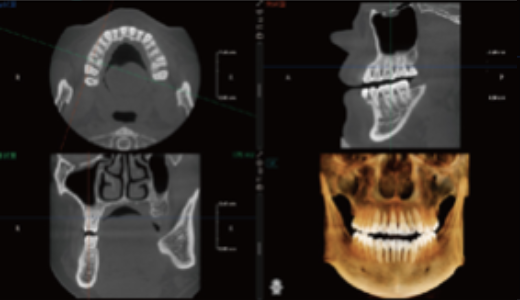

Visualização 3D do Seio Maxilar

Gera automaticamente a estrutura 3D do seio maxilar.

Permite uma observação clara da morfologia do seio e ajuda a avaliar os riscos cirúrgicos em implantes maxilares.

Auxilia na avaliação do volume de enxerto em elevação do seio maxilar